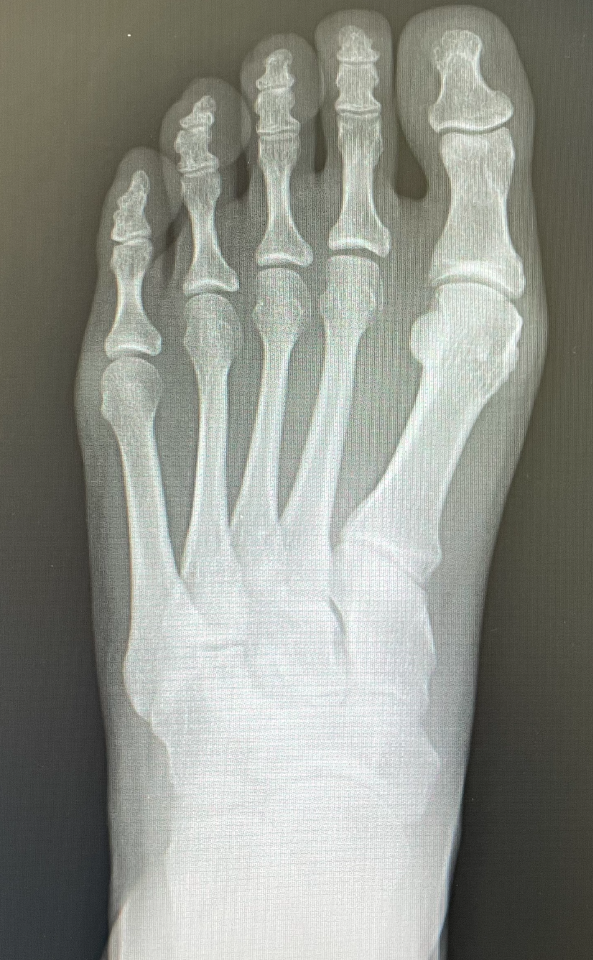

外反母趾による中足骨頭痛は、母趾が外側に変形し、第1中足骨が内反することで、他の中足骨に負担がかかり痛みが生じる症状です。特に、外反母趾が進行すると内側縦アーチや横アーチが扁平化し、足全体のバランスが崩れ、第2・第3中足骨頭に過度な負荷がかかります。外反母趾によって母趾が短くなり、相対的に伸びた第2・第3中足骨頭がtoe off時に強く地面に接するのも痛みの原因となります。

平面として捉えるレントゲン画像から実際の状態を想像することがいかに難しいことか、多くの文献でもレントゲンの撮影方法に対して様々な取り組みをしている点からもどの角度で見れば問題がわかるかという足特有の難しさに気付かされます。